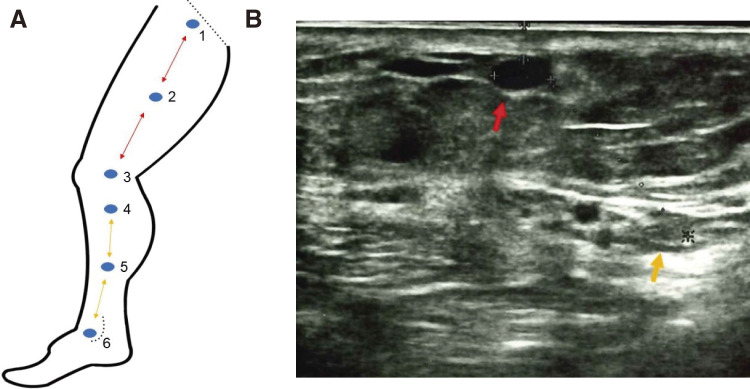

Objectives: This study aimed to quantitatively evaluate peripheral nerve injury (PNI) after varicose vein (VV) surgery using endovenous laser ablation (EVLA). Methods: Overall, 25 cases were analyzed. All patients underwent EVLA of the great saphenous vein (GSV) with or without resection of the varix of the GSV tributaries in stab and avulsion fashion (microphlebectomy). For evaluation of PNI, the current perception threshold (CPT) was measured preoperatively at 1 week, 1 month, 3 months, and 6 months postoperatively. In each leg, CPT was measured at 6 points. PNI was defined as >40% elevation from preoperative data. Results: A significant elevation in CPT was observed at 2 points (knee joint level [P = 0.01] and upper portion of the lower leg [P = 0.008]) 1 week postoperatively. CPT decreased after 1 month and recovered to the same level after 6 months. PNI occurred in 52% and 36% of patients at the knee joint level and upper portion of the lower leg, respectively. Microphlebectomy was indicated as a factor associated with PNI (P <0.01). Conclusions: Although VV surgery using EVLA is less invasive, the occurrence of transient PNI in the early postoperative period should be noted when concomitant microphlebectomy is performed.